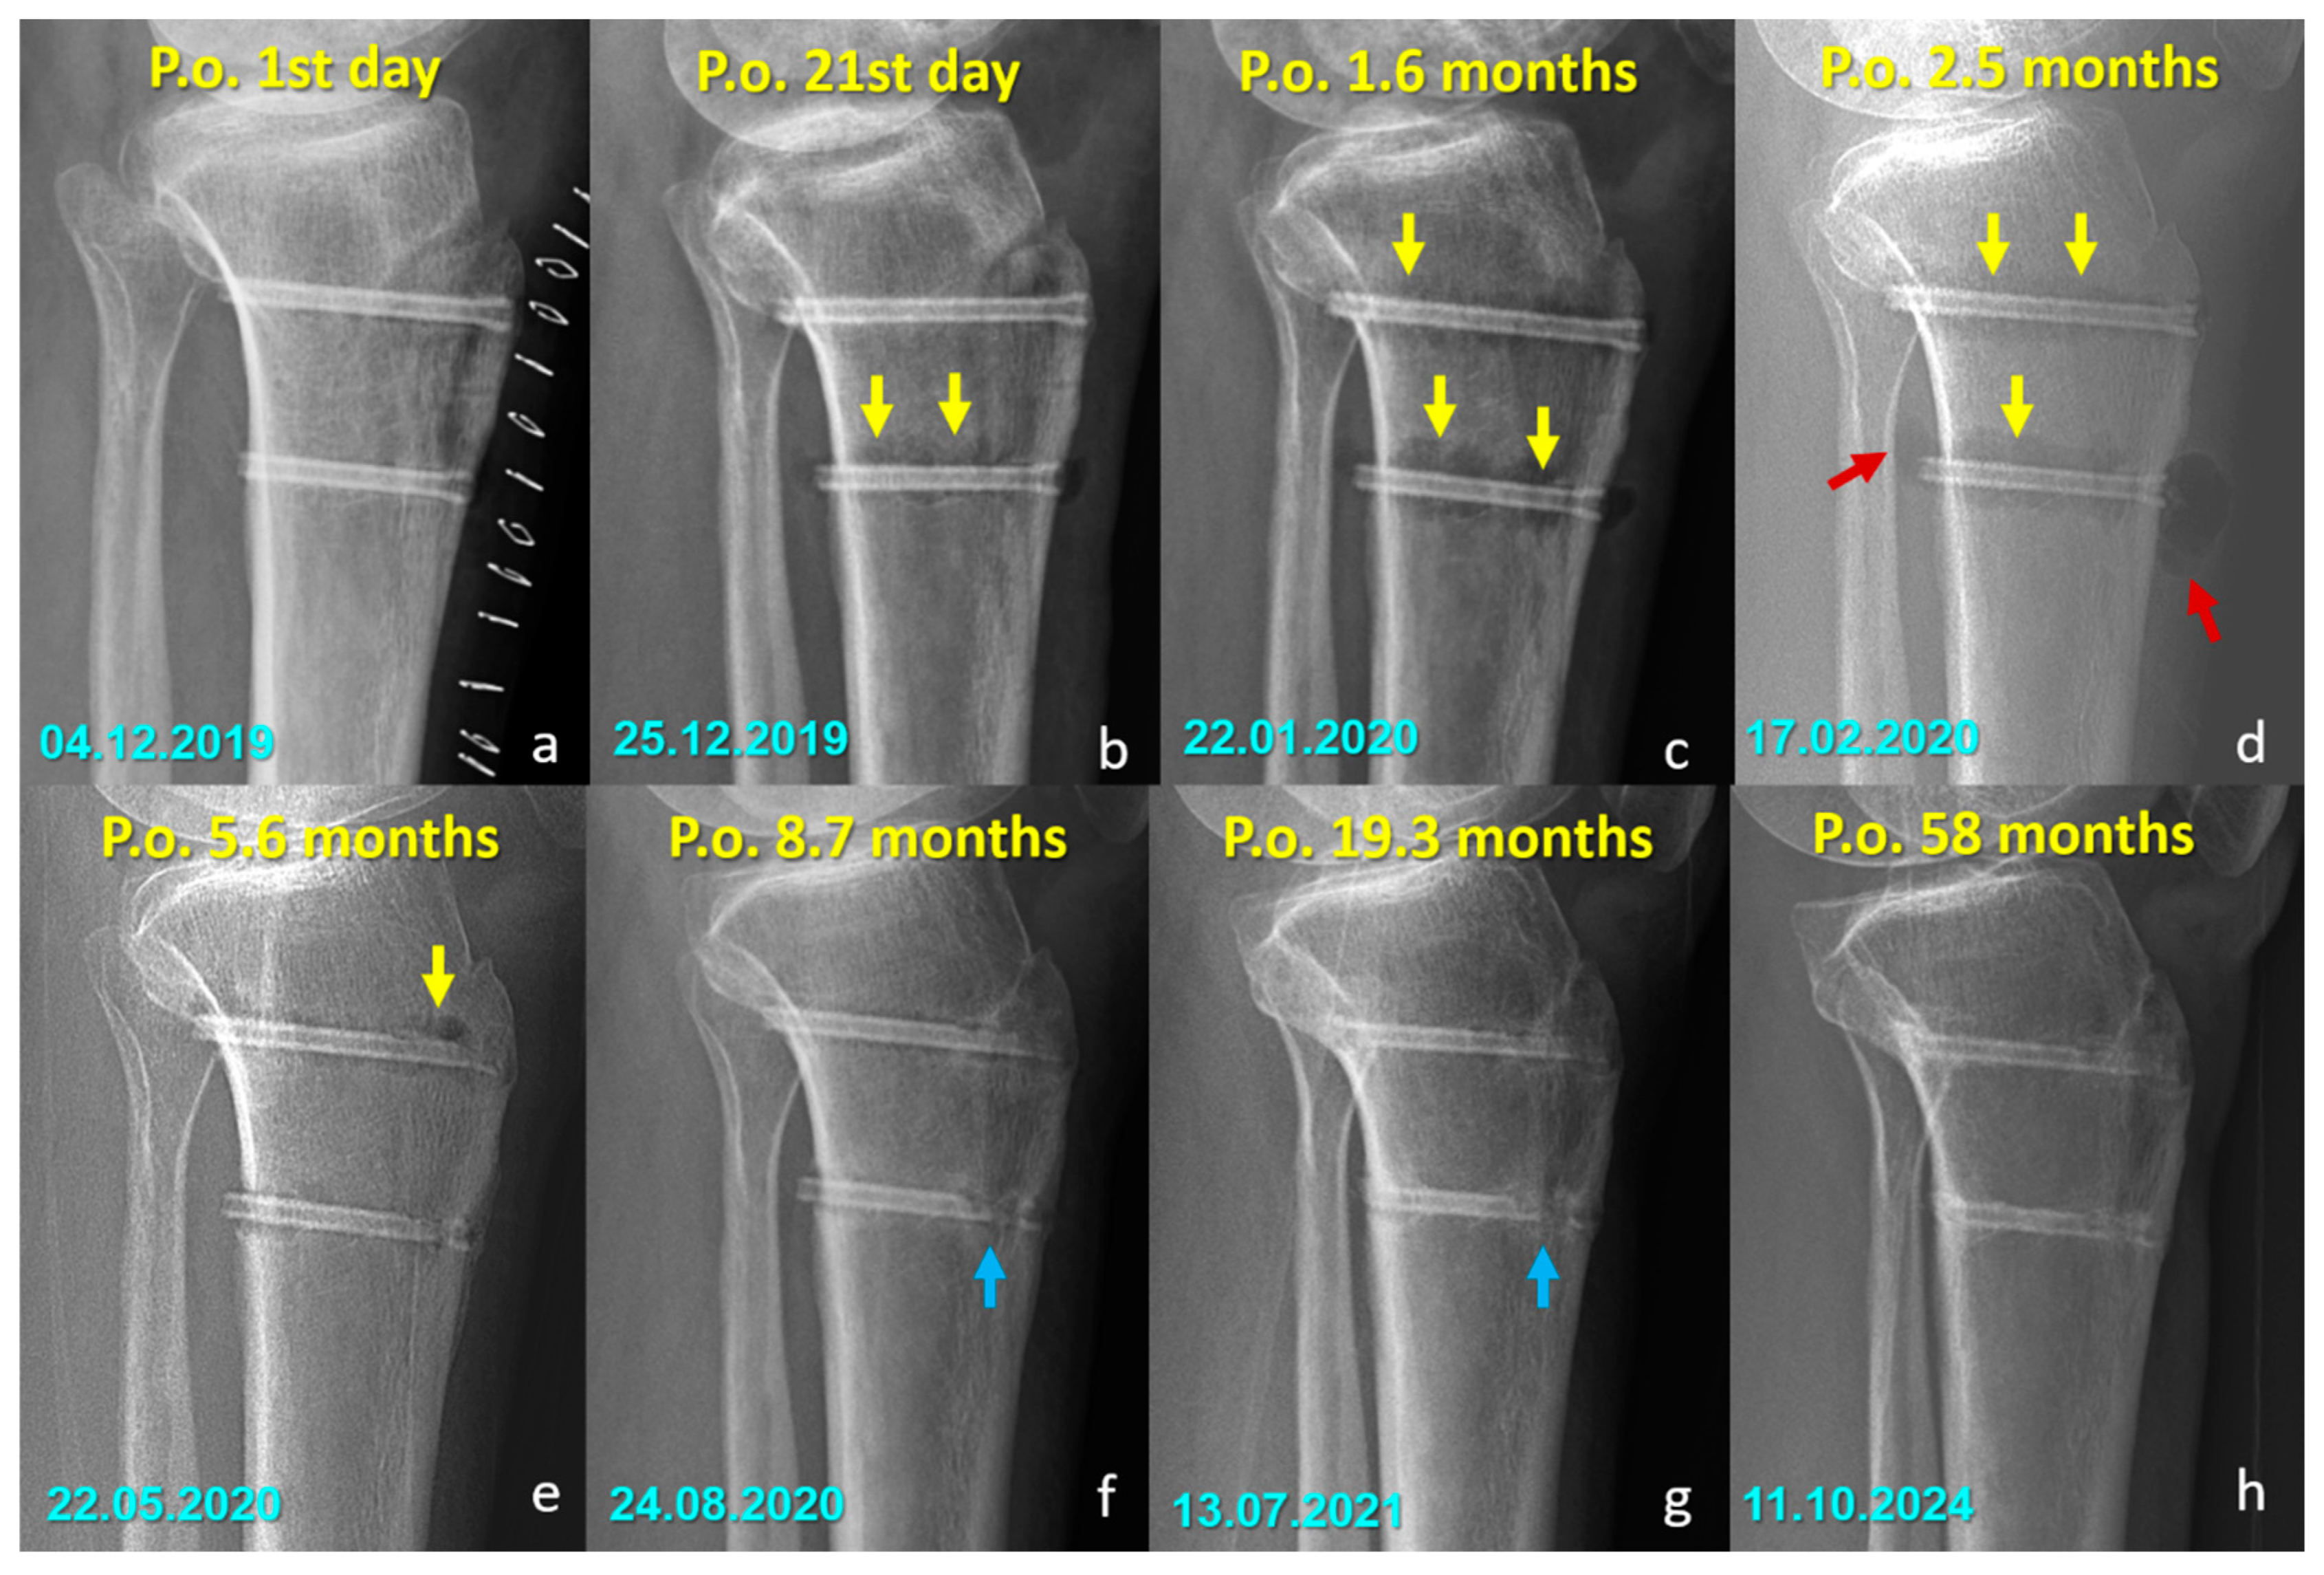

Radiographic Findings in the Mg Screw Group